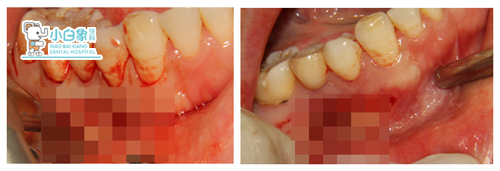

ct确定手术切口及入口位置

不行倒充填+骨粉骨膜

CT定位后:龈缘下5mm行半月形切口,翻瓣,见骨缺后扩大,刮除,清创,截根,置骨粉盖膜,缝合。

根尖倒充填+置PRF膜

倒充填不置填充物